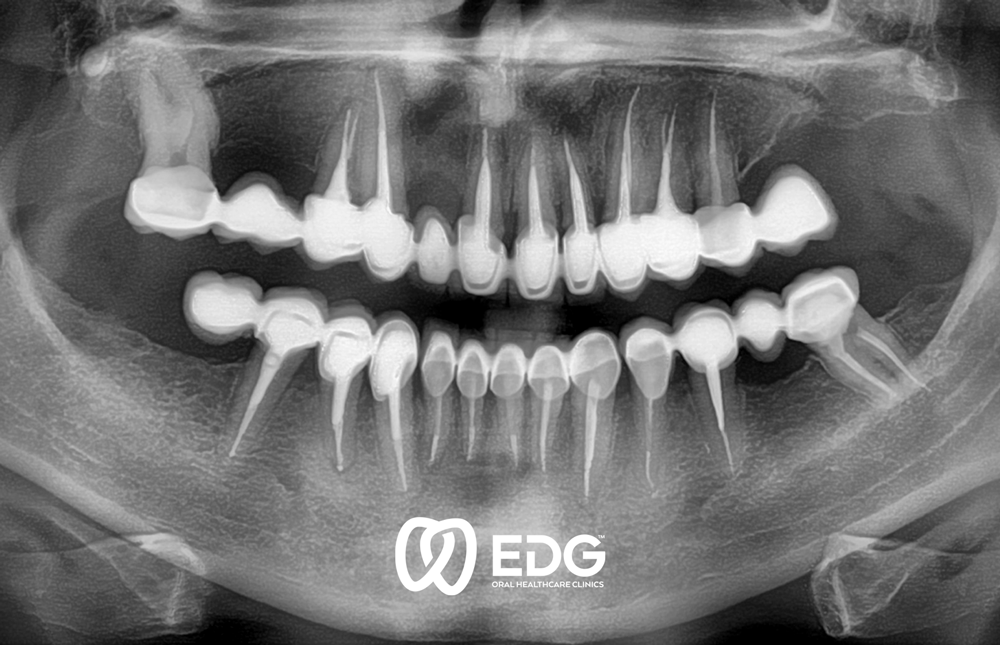

Η απώλεια ενός δοντιού μπορεί να οφείλεται σε διάφορους λόγους: τερηδόνα, περιοδοντίτιδα ή τραυματισμοί και ατυχήματα. Στην Κλινική Διεύθυνση Προσθετικής, προσφέρουμε στους ασθενείς μας ενημερωμένη περίθαλψη, η οποία γίνεται σύμφωνα με τα αισθητικά και λειτουργικά πρότυπα και τις ατομικές απαιτήσεις. Επιμένουμε στην αδιαχώριστη σύνδεση μεταξύ της μορφής και της λειτουργίας των οδοντικών προσθετικών. Μόνο η λειτουργικά καλή εργασία οδηγεί σε καλά αισθητικά αποτελέσματα. Για την επιλογή και την κατασκευή της οδοντικής πρόσθεσης, αντικειμενικά κριτήρια διαδραματίζουν ρόλο καθώς και ο τύπος και η ηλικία του ασθενούς. Η πολύπλοκη προσθετική ανασυγκρότηση της οδοντοστοιχίας απαιτεί ακριβή και εκτεταμένη διάγνωση προτού ξεκινήσουν τα επανορθωτικά μέτρα. Για να γίνει αυτό, απαιτείται μια ενδελεχής ιατρική αναισθησία, καθώς και η ραδιοδιαγνωστική και η χρήση σύγχρονων μεθόδων για τον ακριβή προσδιορισμό της θέσης των δοντιών και της κίνησης της κροταφογναθικής άρθρωσης. Για την προσθετική αποκατάσταση, χρησιμοποιούμε σύγχρονη τεχνολογία στεφάνης και γέφυρας, μερικές φορές και πλήρεις προθέσεις και εμφυτεύματα.

Η προσθετική αποκατάσταση πρέπει να πληροί λειτουργικές αλλά και αισθητικές απαιτήσεις. Θέλουμε να κάνουμε την προσθετική εφαρμογή στην υπόλοιπη οδοντοστοιχία χωρίς να αποσπά την προσοχή. Ταυτόχρονα, οι αισθητικές απαιτήσεις μας για την προσθετική φροντίδα είναι πολύ υψηλές.